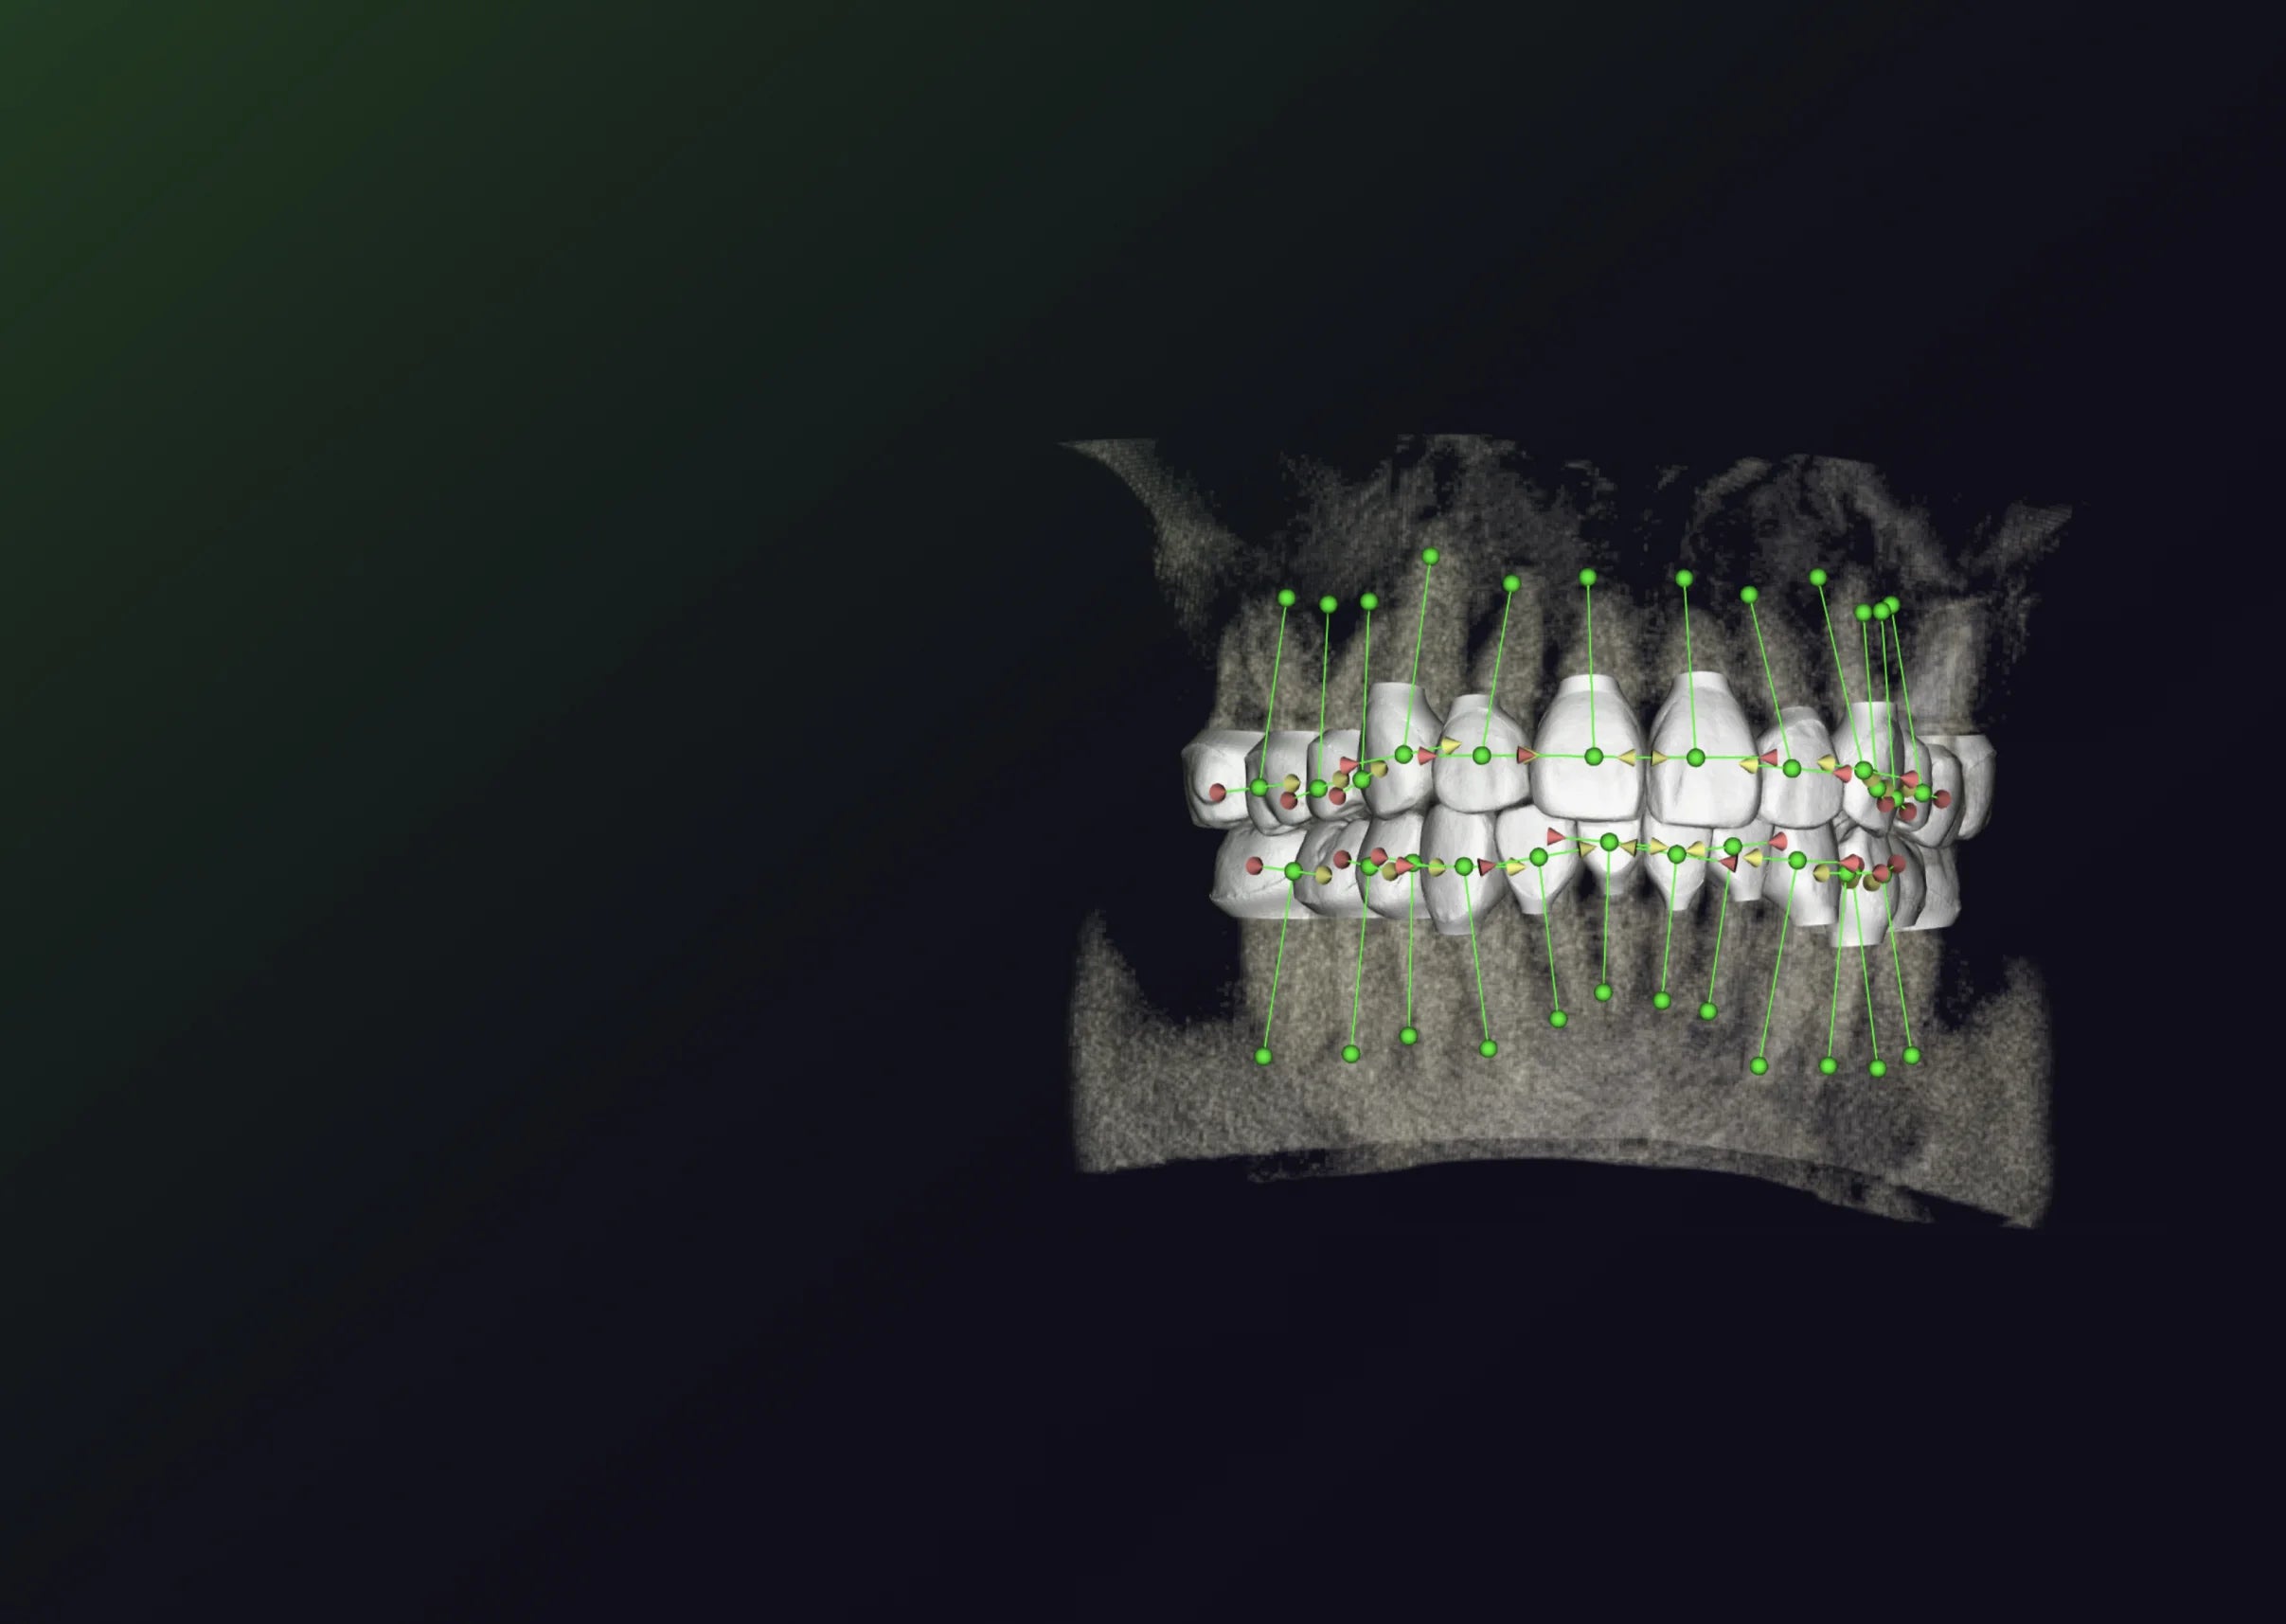

Teeth attachments for clear aligners are small, tooth-colored buttons or bumps that are temporarily bonded to specific teeth during orthodontic treatment. They are made of a composite material and are designed to help the clear aligners apply more precise force to certain areas of the teeth that need more movement.

These attachments help aligners grip the teeth more effectively and facilitate complex movements that may not be achievable with aligners alone.

- Improve Tooth Movement – They provide additional leverage for moving teeth in difficult directions (e.g., rotations, extrusions, or intrusions).

- Enhance Aligners' Grip – Since aligners are smooth and fit snugly, attachments create points for aligners to "push" against.

- Correct Complex Cases – More challenging tooth movements (such as correcting deep bites, crossbites, or large gaps) often require attachments.